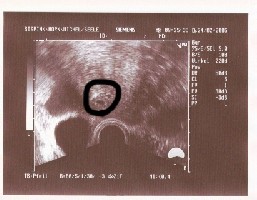

@all:ich habe mich wohl ein wenig rar gemacht.. :-? aber nur weil ich tierische Angst vor einer FG habe.heute war nun mein erster US Termin.Mann konnte zwar 2!! Fruchthüllen erkennen,aber mehr sieht man wohl auch nicht bei 5+1.

Ob es nun wirklcih Zwillinge werden weiß ich nicht,Da Bispink sagt das sich meistens(aber nicht immer)das größere durchsetzt,und bei mir ist das der Fall das beide unterschiedlich groß sind.

heute ist ja theoretisch Transfer +19 und der wert liegt bei 4558.

Hier mein erstes US Bild.Oder meint ihr man hätte schon mehr sehen müssen??(immer noch Angst habe)

Us bild bei 5+1

<br />hcg wert 4558

erstmal :knuddel: für Dich kann Deine Angst verstehen, es wird diesesmal alles gut gehen!!!

Der Wert ist doch auch toll! *dd*

Es muss nicht immer gleich auf den US soviel erkennbar sein, das ist von Frau zu Frau unterschiedlich...